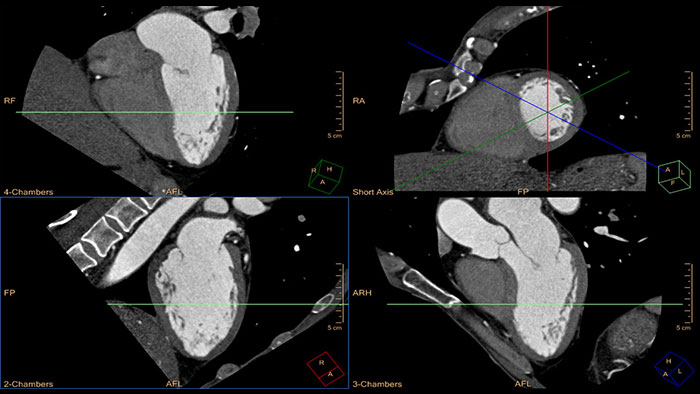

- Cardiac Viewer

-

CT Cardiac Viewer

Quick cardiac visualization

Provides a set of tools for the visualization of one or multiple cardiac phases using original images or MPR\MIP images in axial, coronal, sagittal or dedicated cardiac axes (short axis, horizontal long axis, and vertical long axis).

Benefits

- Automatic removal of the rib-cage structures enables a 3D anatomical Volume Rendering image of the heart and the large blood vessels connected to it.

- The Viewer supports basic measurements as well as basic ventricular functional analysis based on “Area-Length” method to estimate end systolic volume (ESV), end diastolic volume (EDV), cardiac output (CO), and ejection fraction (EF).